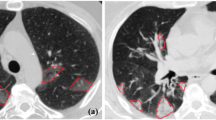

The ongoing COronaVIrus Disease 2019 (COVID-19) pandemic carried by the SARS-CoV-2 virus spread worldwide in early 2019, bringing about an existential health catastrophe. Automatic segmentation of infected lungs from COVID-19 X-ray and computer tomography (CT) images helps to generate a quantitative approach for treatment and diagnosis. The multi-class information about the infected lung is often obtained from the patient’s CT dataset. However, the main challenge is the extensive range of infected features and lack of contrast between infected and normal areas. To resolve these issues, a novel Global Infection Feature Network (GIFNet)-based Unet with ResNet50 model is proposed for segmenting the locations of COVID-19 lung infections. The Unet layers have been used to extract the features from input images and select the region of interest (ROI) by using the ResNet50 technique for training it faster. Moreover, integrating the pooling layer into the atrous spatial pyramid pooling (ASPP) mechanism in the bottleneck helps for better feature selection and handles scale variation during training. Furthermore, the partial differential equation (PDE) approach is used to enhance the image quality and intensity value for particular ROI boundary edges in the COVID-19 images. The proposed scheme has been validated on two datasets, namely the SARS-CoV-2 CT scan and COVIDx-19, for detecting infected lung segmentation (ILS). The experimental findings have been subjected to a comprehensive analysis using various evaluation metrics, including accuracy (ACC), area under curve (AUC), recall (REC), specificity (SPE), dice similarity coefficient (DSC), mean absolute error (MAE), precision (PRE), and mean squared error (MSE) to ensure rigorous validation. The results demonstrate the superior performance of the proposed system compared to the state-of-the-art (SOTA) segmentation models on both X-ray and CT datasets.

Graphical abstract